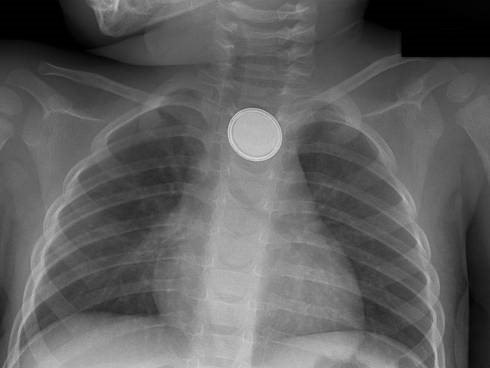

A baby was playing unattended and suddenly developed respiratory distress. Based on the X-ray provided, where is the foreign object most likely located?

Explanation: ***Esophagus*** - The frontal X-ray shows a **coin-shaped foreign body** that is oriented in the **coronal plane** (flat face visible), which is characteristic of an object lodged in the esophagus. - The foreign body is located in the **upper mediastinum**, directly in the known anatomical path of the esophagus, causing respiratory distress due to **extrinsic compression** of the trachea or aspiration. *Trachea* - Foreign bodies in the trachea, especially flat objects like coins, typically orient themselves in the **sagittal plane** (on edge) due to the C-shaped cartilaginous rings. - While tracheal foreign bodies can cause respiratory distress, the orientation on the image is inconsistent with a tracheal location. *Right main bronchus* - The **right main bronchus** is the most common site for aspirated foreign bodies in children due to its wider diameter and more vertical orientation. - However, foreign bodies in the bronchus would typically show air trapping or atelectasis on chest X-ray, and the location and orientation of this object in the upper mediastinum are not consistent with bronchial placement. *Gastrointestinal tract* - The foreign body is located in the **chest cavity**, well above the stomach and intestines. - If a foreign body reaches the gastrointestinal tract, it would typically be beyond the esophagus and would not usually cause acute respiratory distress. *Below diaphragm* - The diaphragm separates the chest cavity from the abdominal cavity. The foreign body is clearly visible within the **chest cavity**, high up in the mediastinum. - A foreign body below the diaphragm in the gastrointestinal tract would not result in the appearance or the acute respiratory distress described without other symptoms.